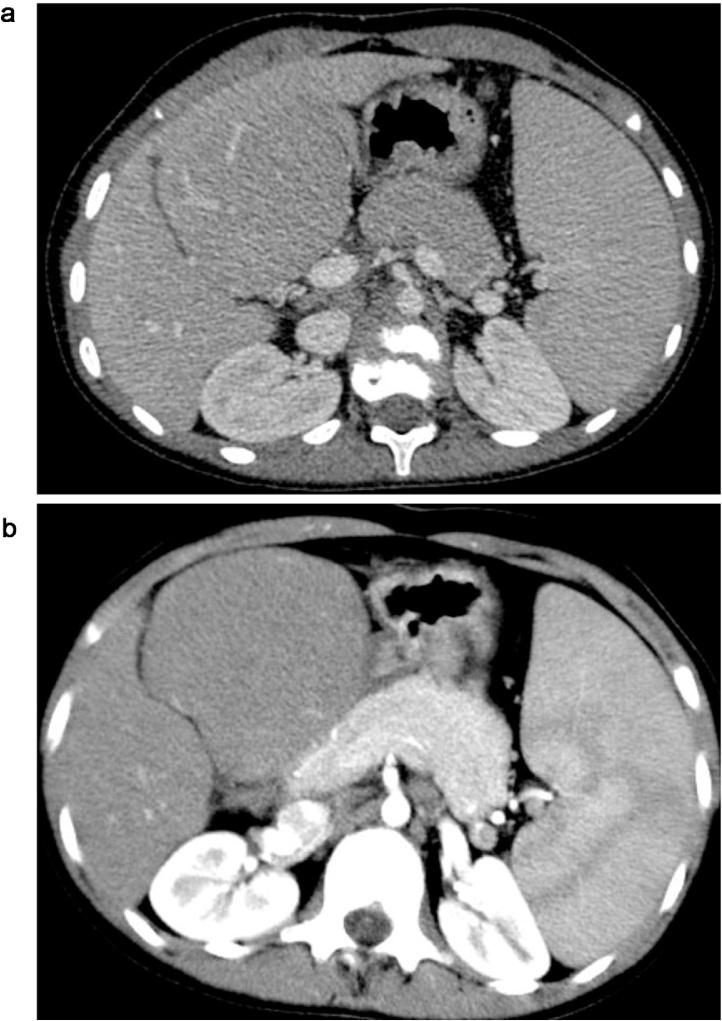

PRESENTATION OF CASE

A 15 year-old girl with Alagille syndrome was referred for liver transplantation. She developed severe cirrhosis with refractory ascites. In the pre-transplant evaluation, imaging studies disclosed liver atrophy with a high density pseudotumor in the segment 4, raising the possibility of a hepatocellular carcinoma. However, behavior of the lesion was highly suggestive of focal compensatory hyperplasia surrounded by an atrophic liver. The patient was registered on the waiting list.

病例介绍

一名15岁患有阿拉吉尔综合征的女孩被转诊进行肝移植。她出现了严重的肝硬化并伴有难治性腹水。在移植前评估中,影像学检查显示肝脏萎缩,在肝段4有一个高密度假瘤,增加了肝细胞癌的可能性。然而,该病变的表现高度提示为被萎缩肝脏包围的局灶性代偿性增生。该患者被列入等待名单。